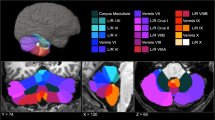

We then identified percent volume loss to the cerebellum for each participant in the entire pTBI group (n = 193) using the automated anatomical labeling (AAL). All participants with damage to the cerebellum were selected (Cerebellar Group; n = 24). Note that this cerebellar group included subjects with pTBIs not restricted to the cerebellum (see Fig. 1). Participants with damage primarily to the right cerebellum (r cerebellum; n = 8), left cerebellum (l cerebellum; n = 6) or bilateral cerebellum (b cerebellum; n = 6) were identified (see Fig. 1). Participants with a unilateral cerebellum lesion (right or left) who also had bilateral supra tentorial cortical lesions were excluded from further analysis (n = 4). All of the pTBI participants without a lesion in the cerebellum were selected as a control group (Other pTBIs; n = 169, see Fig. 2). This group was then subdivided into patients with a unilateral left cortical lesion (l Cortical; n = 51), a unilateral right cortical lesion (r Cortical; n = 65) or bilateral cortical lesions (b Cortical; n = 53) for additional analyses (see Fig. 2). To test the lateralization effect on the ToM tasks, both bilateral cortical and cerebellum groups were excluded. Neurologically healthy veterans also served as a comparison group (No Lesion group; n = 52).

Lesion overlay maps of participant with cerebellar lesion (n = 24) grouped by lesion location. Numbers on the top of the brain slices indicate the z coordinates (MNI) of each axial slice. The color indicates the number of veterans in the group with damage to a given voxel. Images are in radiological space (i.e. right is left). For interpretation of the references to color in this figure legend, the reader is referred to the web version of this article.